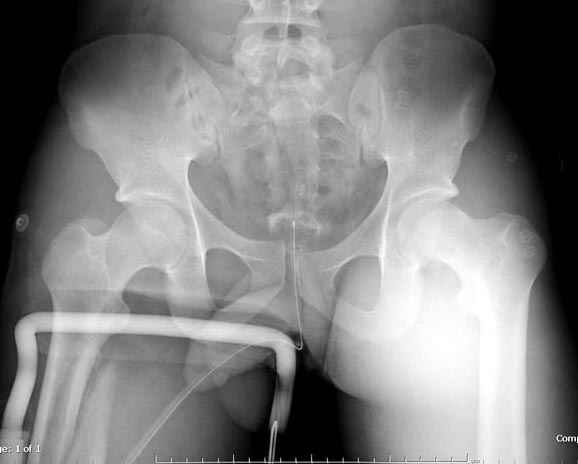

Здесь слайды случая больного с политравмой, включающей сегментарный перелом бедра и повреждение таза с нарушением тазового кольца, разрыв симфиза и перелома крестца зон 2 и 3.

На множественных слайдах важные моменты операции. Хотел бы подчеркнуть, как важно иметь возможности всех необходимых ренгенограмм, включая компютерную томографию и стандартных внутритазовых рентгенограмм (инлет и оутлет).